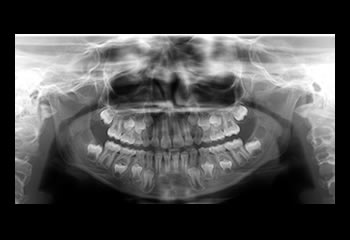

Radiografias Panorâmica

A radiografia panorâmica é um exame útil e bastante prático para complementar o exame clínico no diagnóstico das doenças dos dentes (cáries ou doenças periodontais) e dos ossos da face.